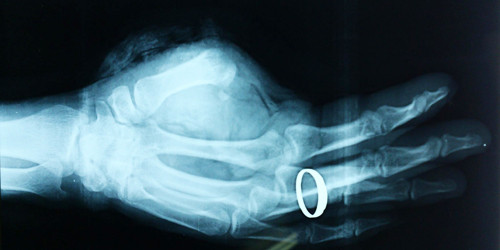

Trước đó, bệnh nhân Lê Văn Cường (SN 1980, trú tại huyện Nghi Lộc, Nghệ An) được người nhà chuyển tới Bệnh viện Chấn thương chỉnh hình Nghệ An trong tình trạng đứt lìa ngón cái tay trái, mất nhiều máu, vết đứt sắc ngọt… Người nhà còn mang theo phần ngón cái bị đứt rời đã được bảo quản lạnh và đưa tới bệnh viện. Qua thăm khám, hội chẩn khẩn cấp và quyết định phẫu thuật nối ngón tay ngay.

| Ca phẫu thuật nối ngón tay thành công đầu tiên tại Nghệ An. |

Thời điểm hiện tại, hơn một tháng phẫu thuật, bệnh nhân đã được xuất viện, dự kiến 3 tháng sau bệnh nhân sẽ được tiếp tục nối gân. Theo giám đốc bệnh viện Chấn thương chỉnh hình Nghệ An thì thành công của ca phẫu thuật nối ngón tay thành công có ý nghĩa lớn với bệnh viện, mở ra khả năng phẫu thuật nối chi cho bệnh nhân khác.